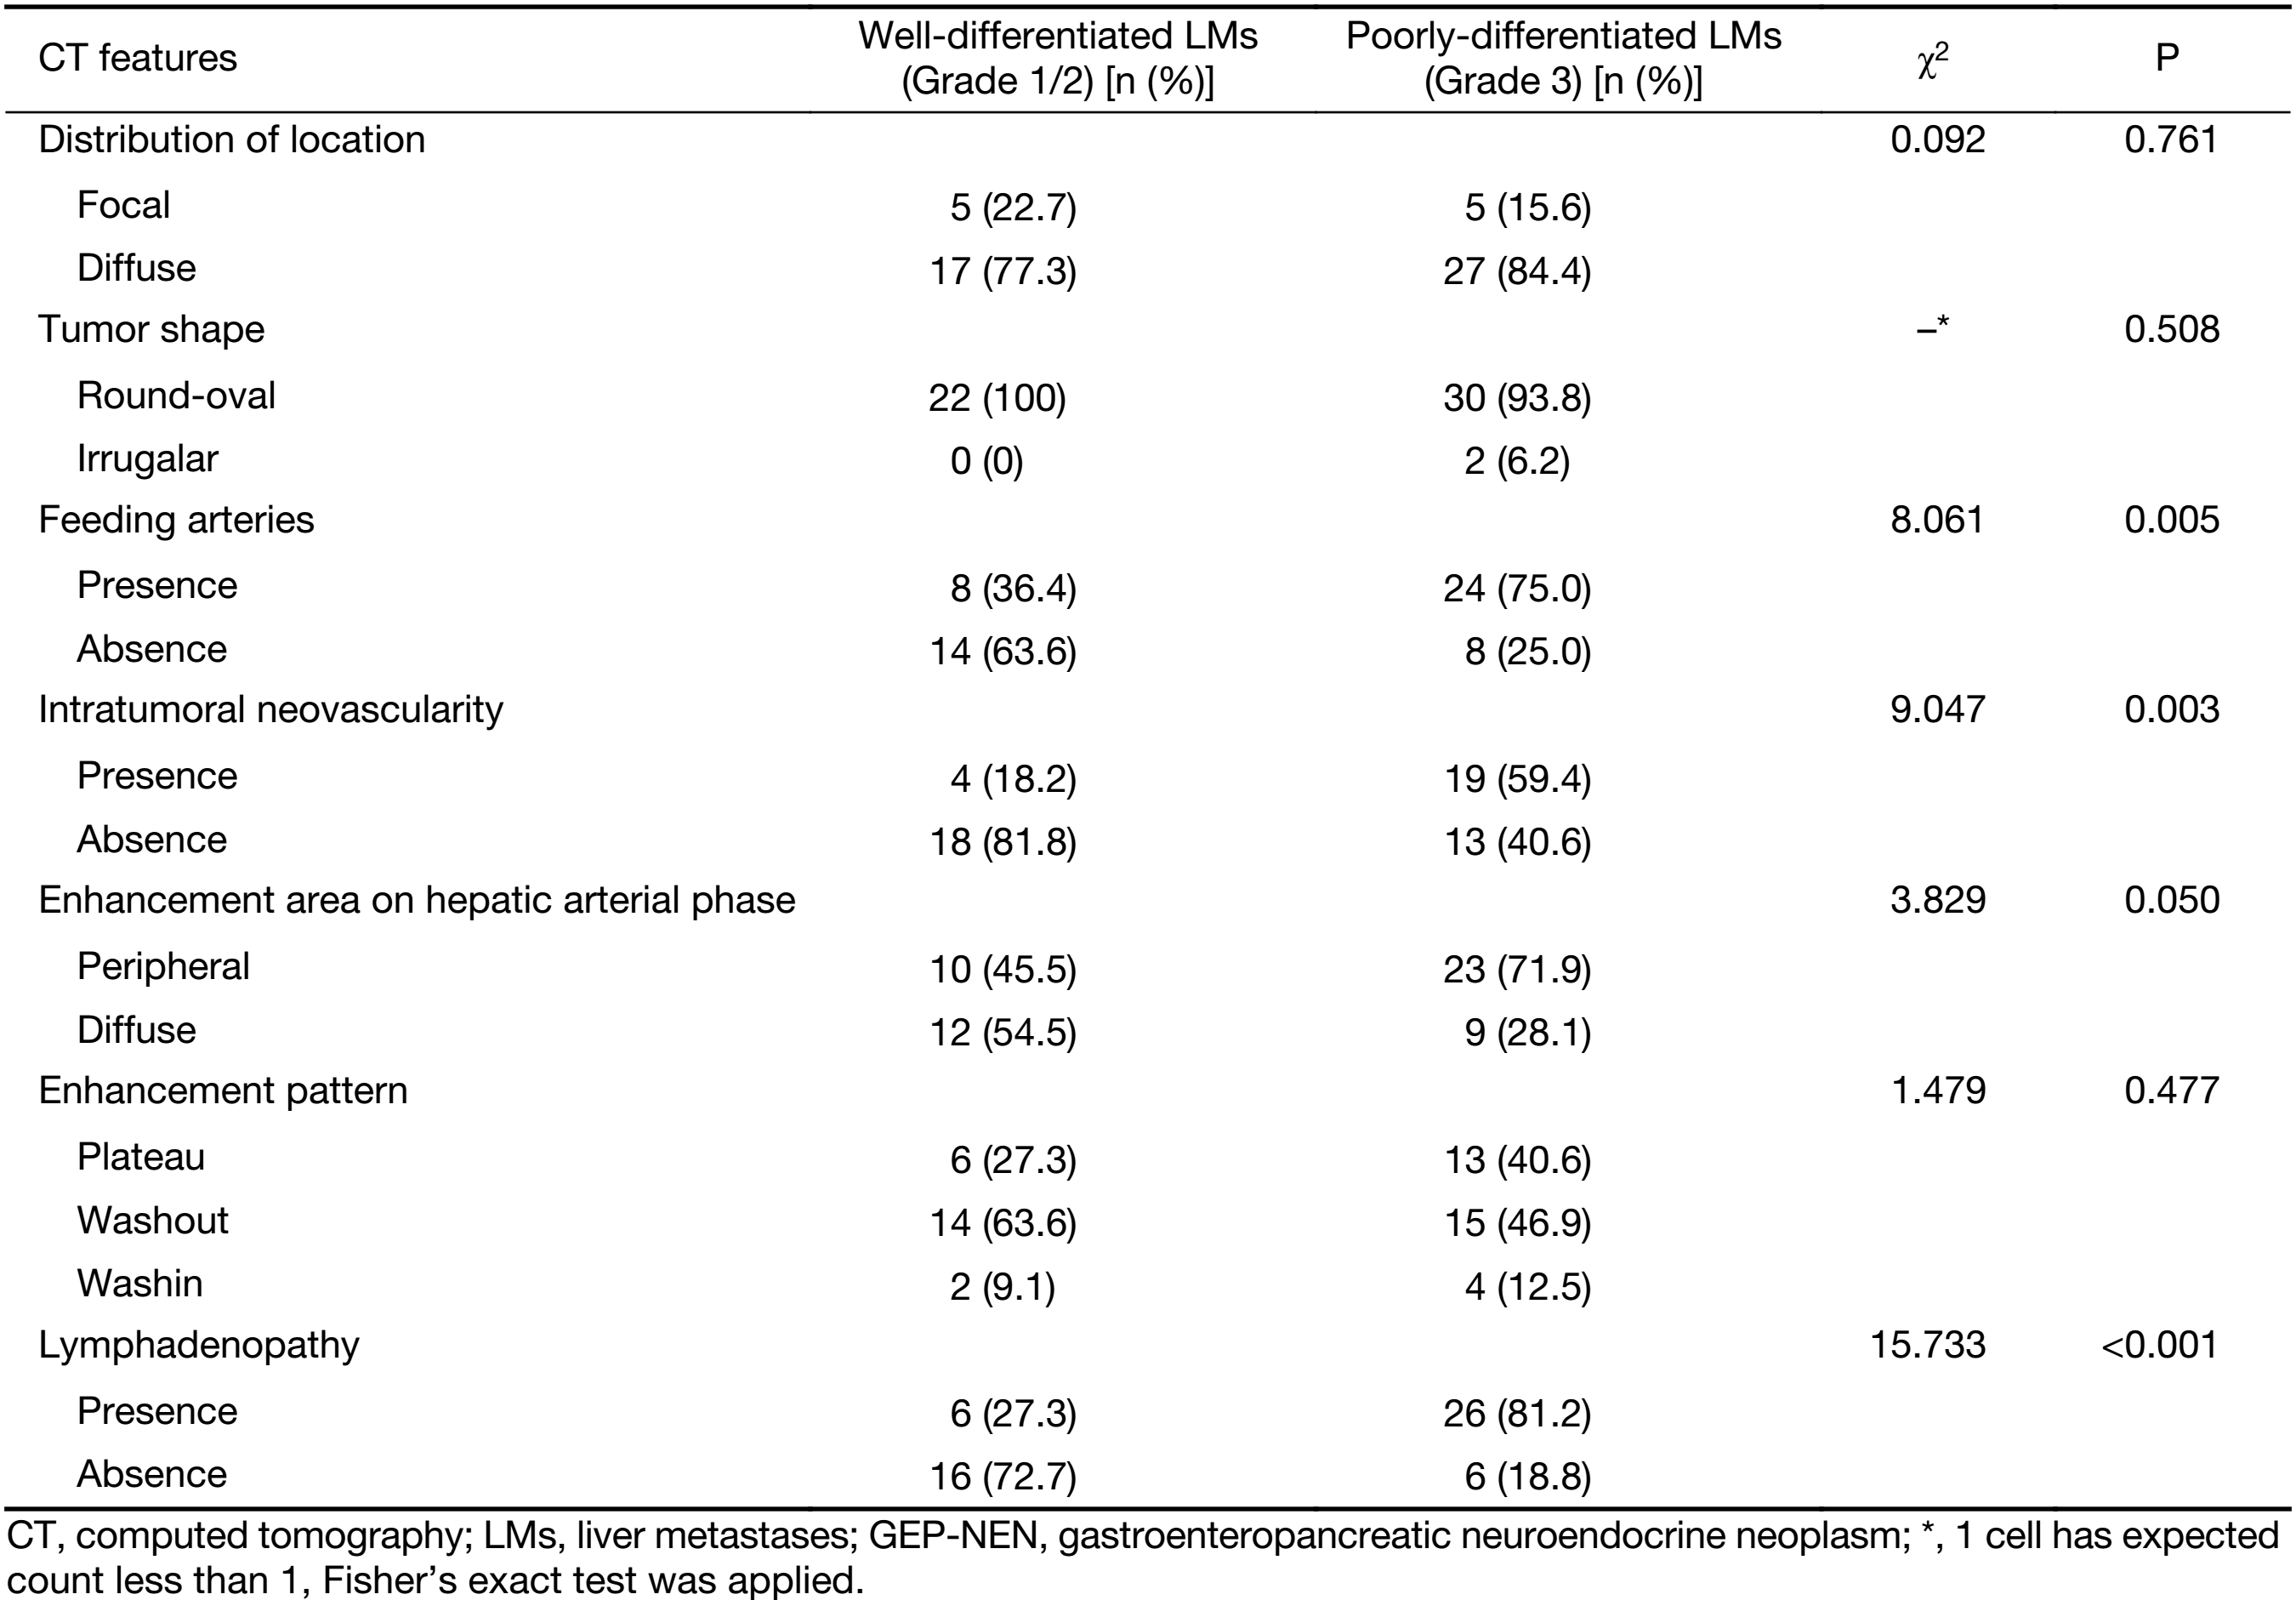

The qualitative image analyses of LMs of well- and poorly-differentiated GEP-NENs are summarized in Table 2. The distribution and shape of tumors were not significantly different between the two groups (P=0.761 and 0.508). All the LMs of GEP-NENs were mainly diffused with a round-oval shape. More feeding arteries and intratumoral neovascularity were found in LMs of poorly-differentiated GEP-NENs than in LMs of well-differentiated GEP-NENs (P=0.005 and 0.003). With regard to the enhancement area, there was no significant difference (P=0.050), and the enhancement pattern was not significantly different (P=0.477). Lymphadenopathy was statistically significant in differentiating LMs of well-differentiated GEP-NENs from poorly-differentiated GEP-NENs (P<0.001), with lymphadenopathy occurring more often in poorly-differentiated GEP-NENs. Representative cases are shown in Figures 2 and 3.

The inter-observer agreement of qualitative image analyses between the two readers was substantial to perfect for all CT features (κ=0.877 for distribution, κ=0.791 for shape, κ=0.776 for feeding arteries, κ=0.645 for intratumoral neovascularity, κ=0.844 for enhancement area in the hepatic arterial phase, κ=0.762 for enhancement pattern, and κ=1.000 for lymphadenopathy).